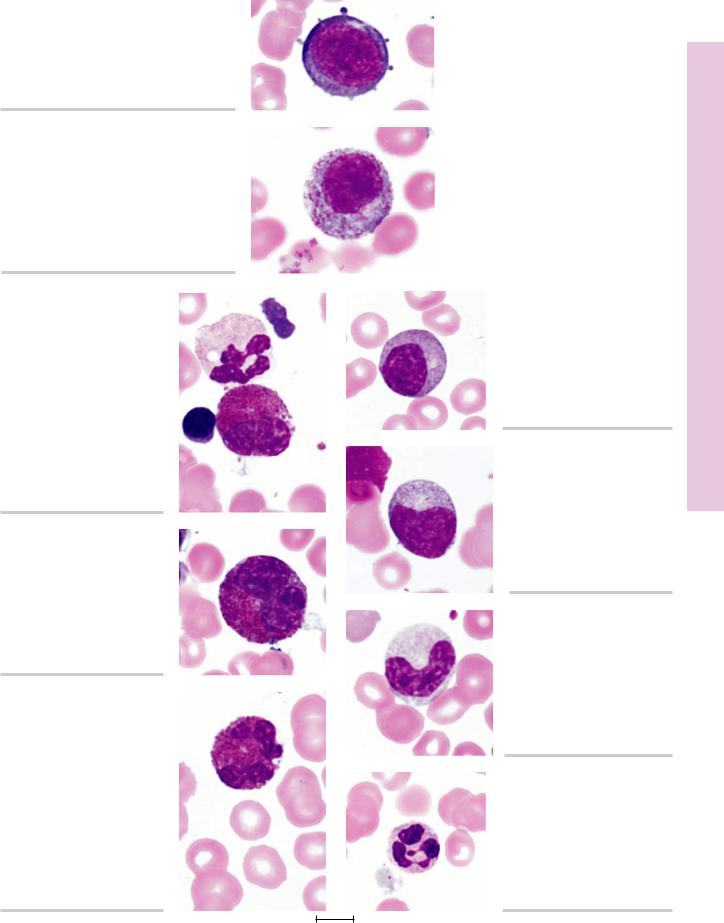

FIGURE 1. Human marrow smear. ×1,325.

Proerythroblast.

FIGURE 2. Human marrow smear. ×1,325.

Basophilic erythroblast.

FIGURE 3. Human marrow smear. ×1,325.

Polychromatophilic erythroblast.

FIGURE 4. Human marrow smear. ×1,325.

Orthochromatophilic erythroblast.

FIGURE 5. Human marrow smear. Methylene blue stain. ×1,325.

Reticulocyte.

FIGURE 6. Human marrow smear. ×1,325.

Erythrocyte.